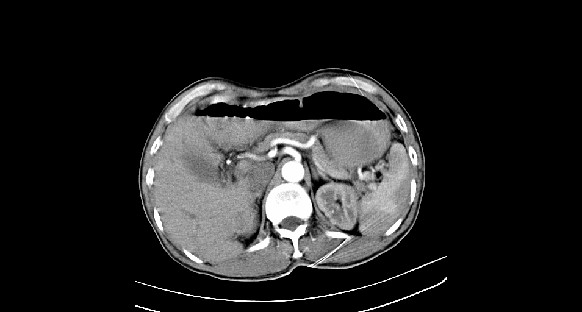

男性,70岁,体检b超发现左肾占位,请各位战友发表一下观点

左肾有两个病灶,且较大的病灶内可见点状钙化灶,增强扫描边缘也是呈渐进性强化,中央部分未见明显强化